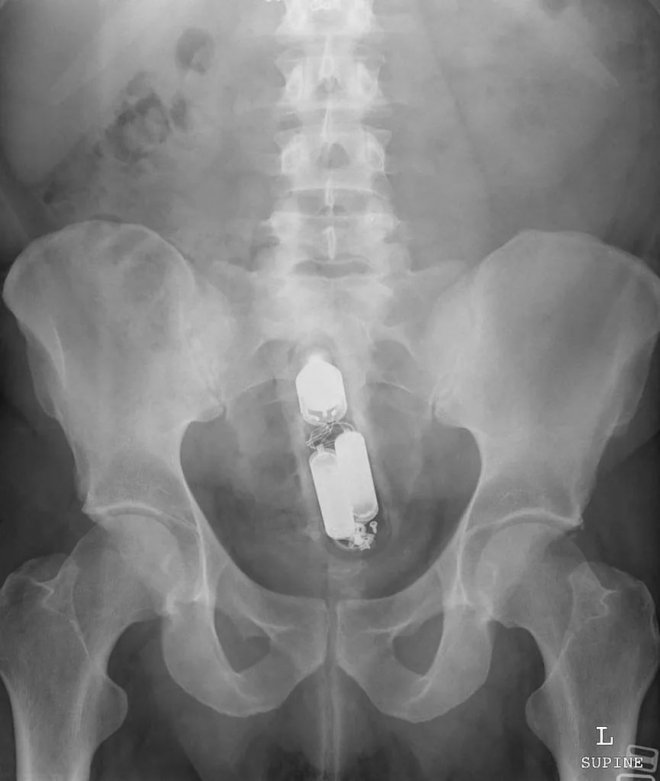

速溶咖啡罐

在直腸中發現了這個東西,而且管子裡還有很多針頭插在蓋子上。咖啡是某知名品牌,但這估計不是廠商希望的曝光方式